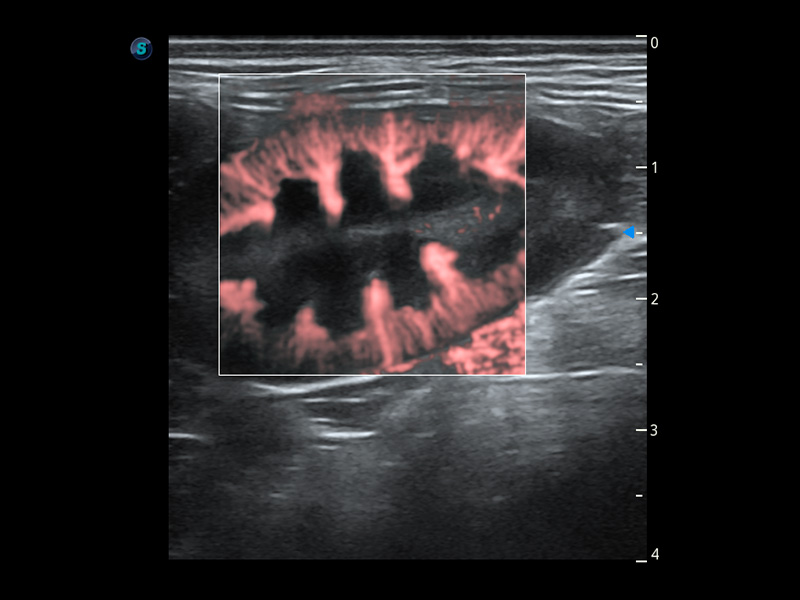

Bright Flow 立体血流成像

在传统二维血流成像的基础上,呈现血流的立体感,具有动感的生命力之美。精确区分不同血管的空间关系,提高了血流的视觉敏感性。

优异的基础图像

(犬)四腔心血流